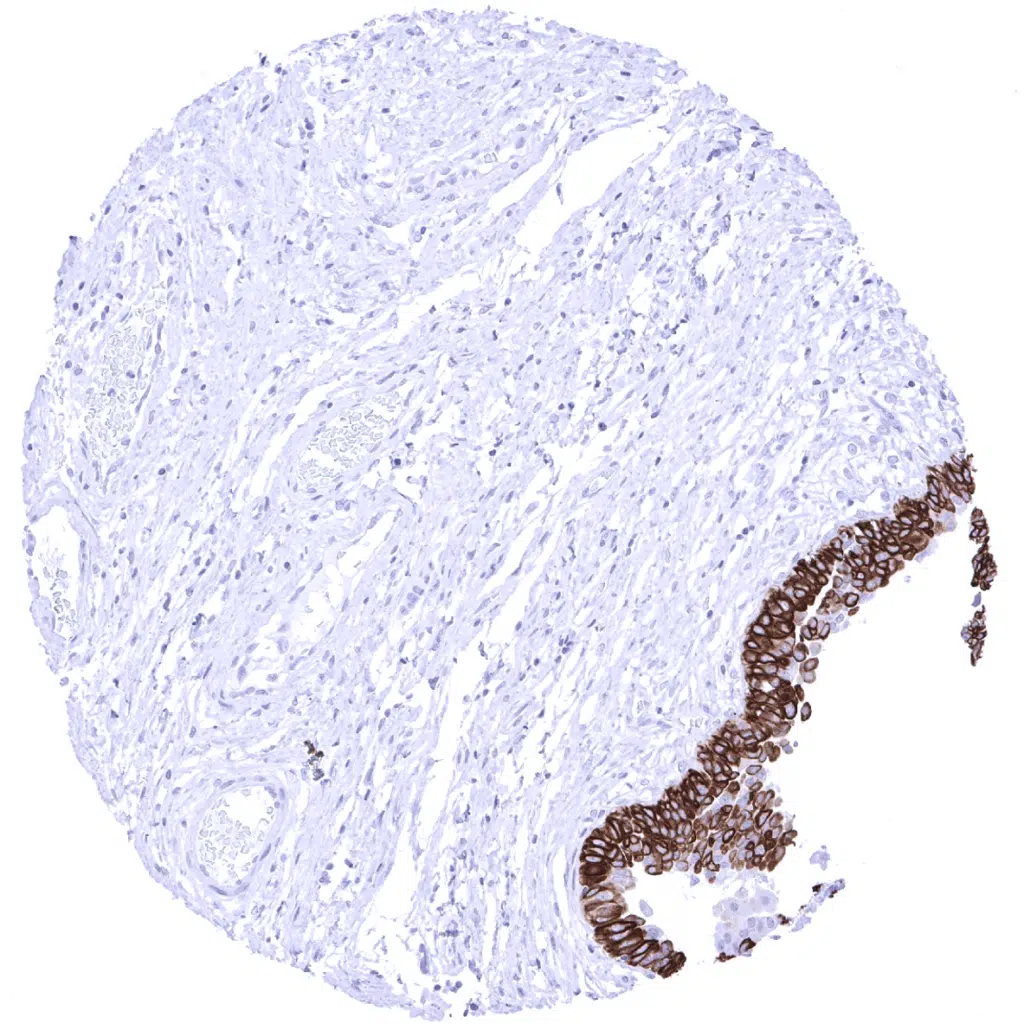

Urinary bladder, urothelium - Cytokeratin 13 is positive in urothelium (except umbrella cells).